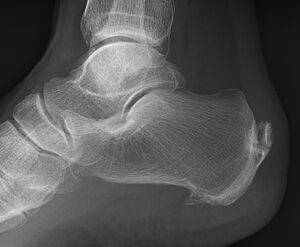

صورة بالأشعة توضح نبتة عظمية على الجوانب الخلفية والسفلية من العقب | |

مهماز العقب (إنگليزية: calcaneal spur، يُعرف أيضاً باسم مهماز الكعب إنگليزية: heel spur)، هو نتوء عظمي ينمو من عظام الكعب.[1] عادة ما يكتشف مهماز العقب بالأشعة السينية.[2] وهو يشكل العرن.

المهماز العقبي الخلفي يقع على الجانب الخلفي للعقب وهو استجابة طبيعية لالتهاب اللفافة الأخمصية على مدار الوقت، لكنه يرتبط أيضاً بالتهاب الفقار المقسط (عادة لدى الأطفال). يتطور المهماز العقبي الخلفي على ظهر الكعب عند مدخل وتر أخيل.[3]

المهماز العقبي السفلي هو تكلس في العقب، الذي يقع أعلى اللفافة الأخمصية عند مدخل اللفافة الأخمصية. غالباً ما يكون المهماز العقبي الخلفي كبياً وملموساً من خلال الجلد وقد يحتاج إلى إزالته كجزء من علاج التهاب وتر أخيل.[3]

يمكن الكشف عن مهماز العقب بالفحص البدني متبعاً بإجراء الأشعة السينية جانبية للقدم.[بحاجة لمصدر]